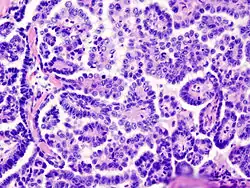

Papillary serous cystadenocarcinoma

Medium power slide of ovarian serous adenocarcinoma stained using haematoxylin and eosin | |

Papillary serous cystadenocarcinomas are the most common form of malignant ovarian cancer making up 26 percent of ovarian tumours in women aged over 20 in the United States.[1]

Papillary serous cystadenocarcinomas may exhibit psammoma bodies upon histopathology.[3]